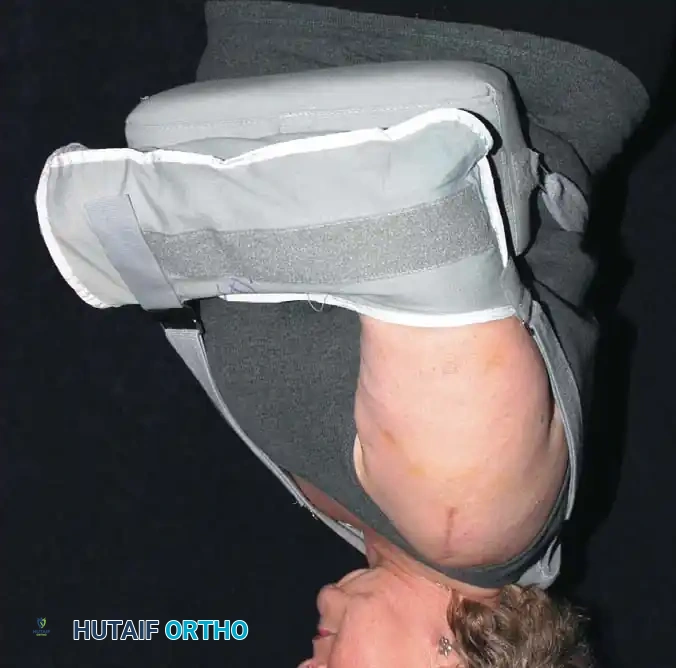

The procedure is typically performed under general anesthesia supplemented with an interscalene regional nerve block for postoperative analgesia. The patient is placed in the beach-chair position with the head secured and the operative arm draped free to allow full manipulation. A mechanical arm holder is highly recommended to control rotation and abduction during the capsular shift.

* The shoulder is immobilized in a sling, often with a small abduction pillow to relieve tension on the superior repair.